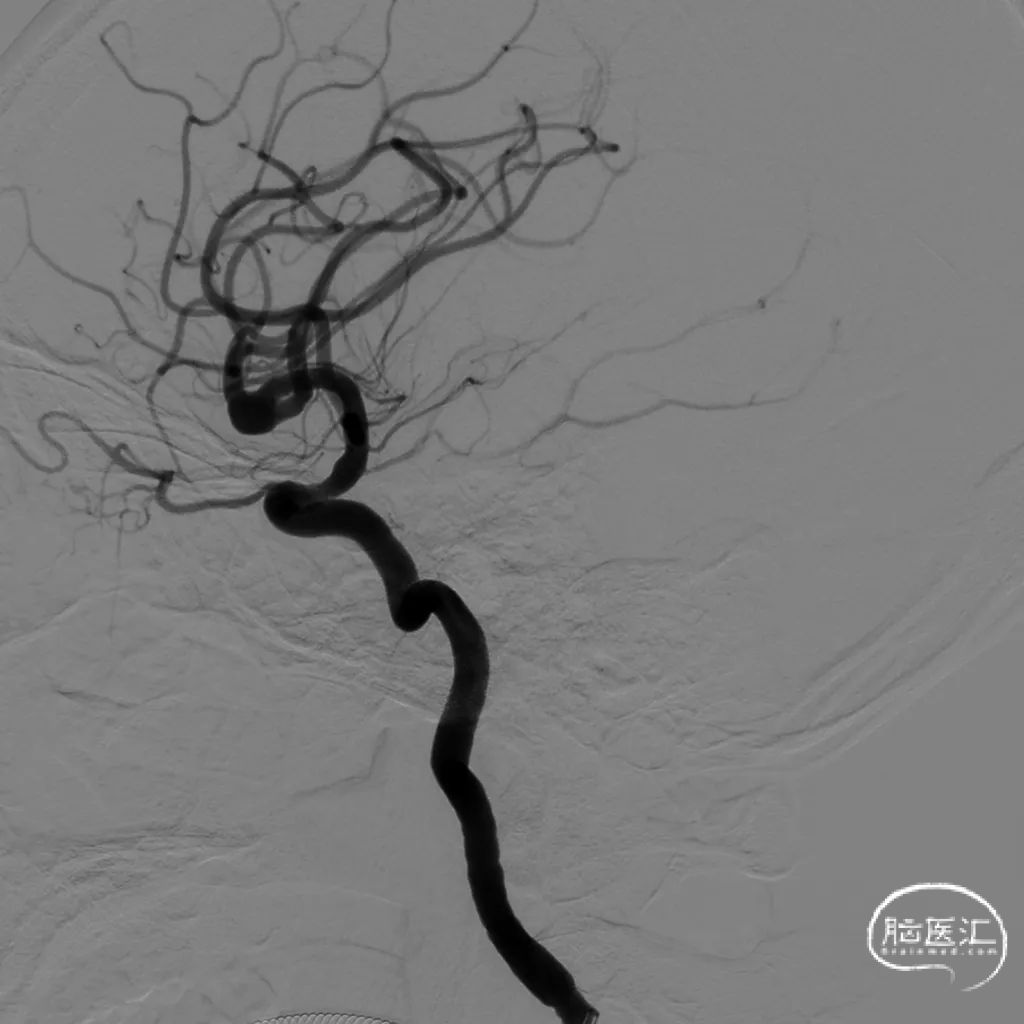

术后即刻正位造影及蒙片:造影显示瘤体致密栓塞,支架贴壁和导流良好。